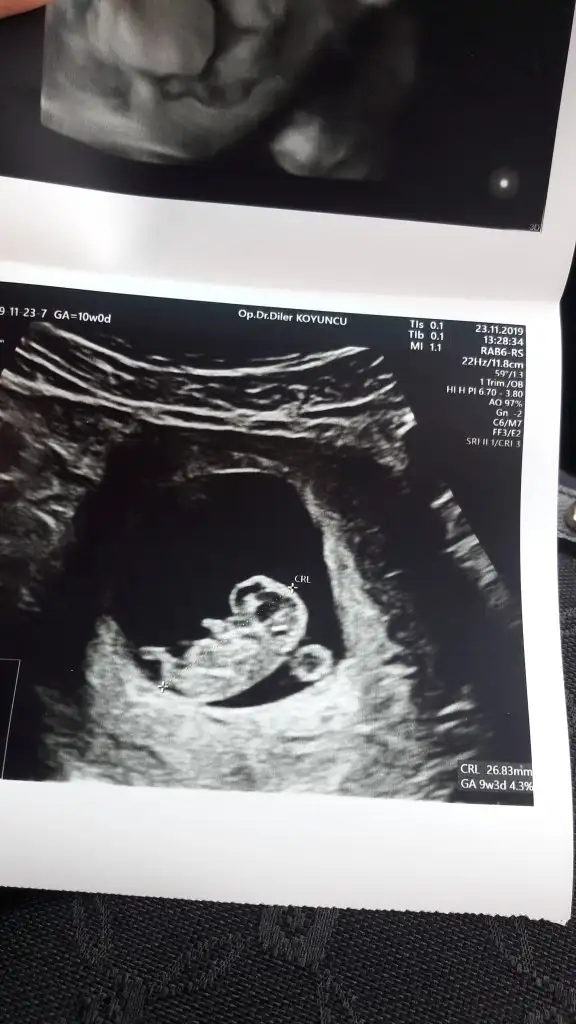

Banada erkek demiştiniz hatta baya net erkek demiştiniz kız diyince doktor şaşırmıştınız bnde çok şaşırmıştım tabi çünkü baya umutlanmıştım 2 kızım var doğal olarak değişik olsun istemiştim tabiki Rabbim in dediği olur ama hala erkek hissediyorum ayrıntılıda pozisyonu tersti cinsiyeti gözükmüyor demişti perinatolog ama 2 doktor kız gibi biride düşük kalitede bir cihazda kız demişti sonra rüyamda bebeğimin isminin koyulduğunu gördüm mavi nüfus kağıdında Ali arif yazıyordu bilemiyorum hala erkek hissediyorum pembe kıyafetleri almama rağmen

az kaldı sonucu görmeye herşey den önce Rabbim sağlıklı ve hayırlı evlatlar nasip etsin bizlere